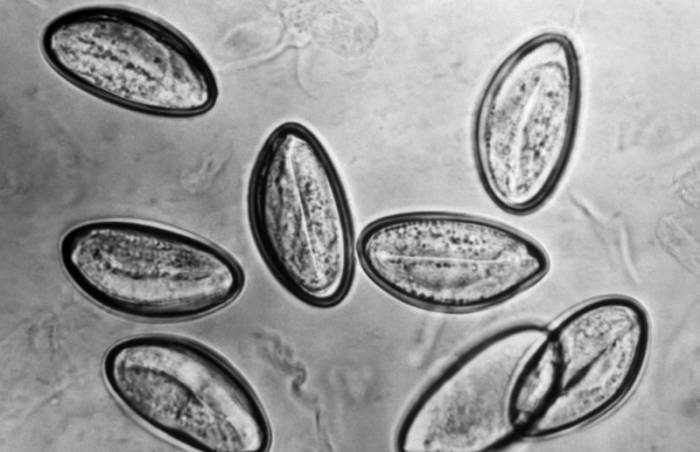

Инструкция «Ивермектина» гласит, что применение препарата является универсальным и успешно избавляет от многих разновидностей глистов, как человека, так и животного. Однако, особенно эффективен препарат для лечения инфекционных заболеваний, провоцируемых круглыми червями.

Средство хорошо проявляет себя в борьбе с такими глистными инвазиями:

Учитывая информацию, предоставленную исследователями, кроме данных форм гельминтов, «Ивермектин» способен активно воздействовать на трематод и ленточных червей. Также средство применяют для избавления от чесоточных клещей и выведения вшей, но в данном случае следует быть осторожным, и не применять препарат без назначения, ведь он негативно воздействует на людей, имеющих слабую иммунную систему.

Выводы. Ивермектин — эффективное противопаразитарное средство, действующее против многих кишечных паразитов (стронгилоидоз, аскаридоз, трихоцефалез, анкилостомоз и др.), эктопаразитов (чесотка, личинки мигрирующих, миаз и др.), а также филяриатоза и онхоцеркоза. Ивермектин обладает хорошим профилем безопасности.